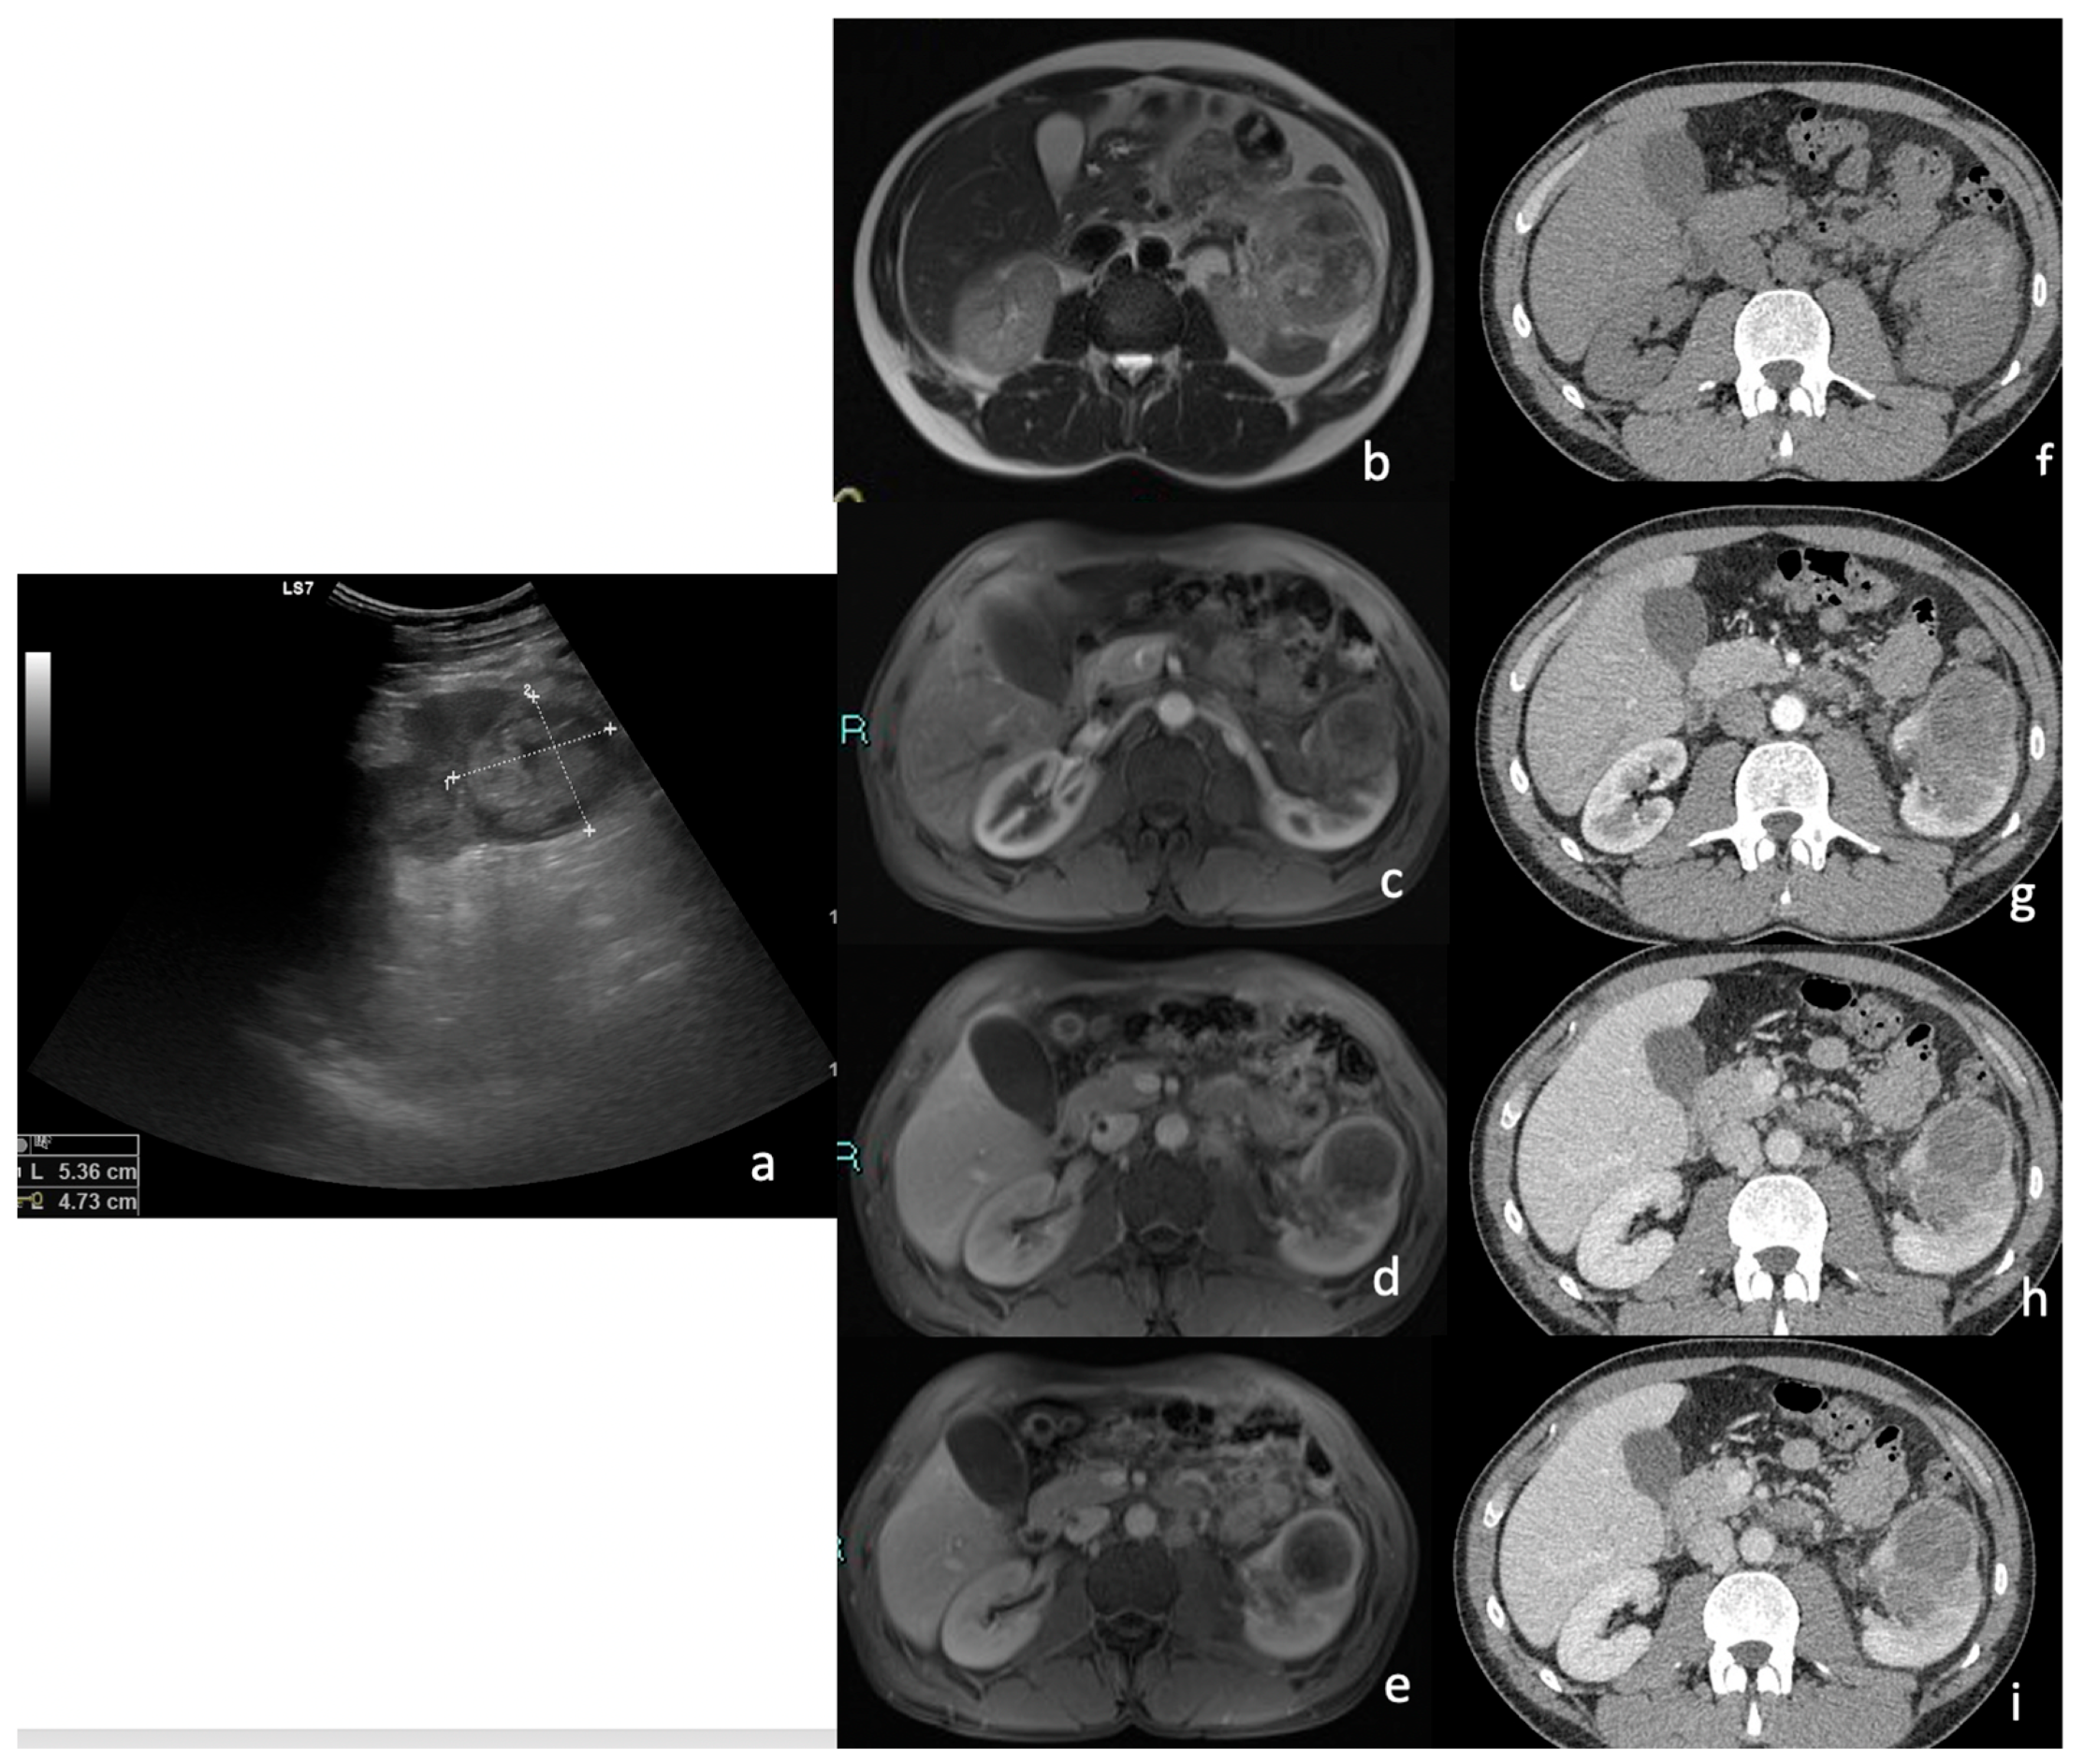

3.1. Ultrasound (US)

3.4. MRI

Signal Intensity, Homogeneity, and Contrast Enhancement